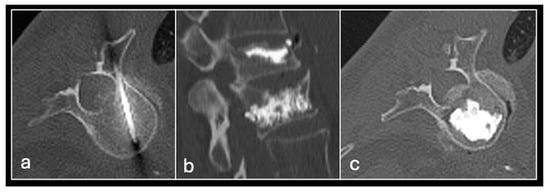

Figure 13. Axial CT (a) showing metastasis in the sacrum. Images (bd) showing sacroplasty with cement in both sacral ala.

Figure 14. CT-guided vertebroplasty showing needle in the vertebral body (a) and sagittal (b) and axial (c) showing cement within the vertebral bodies.

3.5.2. Cement Augmentation

Cement augmentation is the injection of polymethylmethacrylate cement (PMMA) mixture into a bony defect to restore bony structural integrity and provide pain relief. The most common form is vertebroplasty in the context of vertebral compression fractures which—in the setting of oncology—include pathological fractures with underlying myeloma or metastases with resultant pain and disability refractory to conservative treatment. The procedure is also a useful adjunct following percutaneous ablation to restore structural integrity following bone destruction, particularly for larger lesions [33] (Figure 13 and Figure 14).

The most common type of cement augmentation at our centre is vertebroplasty. This is typically performed via a transpedicular approach into the lesion using an 11 G or 14 G bone biopsy needle system. Biopsy samples may be taken with the PMMA and then injected into the defect. A modified procedure is the kyphoplasty in which cement injection is preceded by the inflation of a balloon device in the vertebral body to create space with the cavity then filled with the cement. This is more effective in pain relief and minimises leakage but results in a longer and more expensive procedure [4,63].

Other variants with similar underlying principles include sacroplasty and acetabuloplasty. Complications to be aware of include cement leakage, which can lead to cement thrombosis, pulmonary emboli and compression of adjacent structures [64,65]. Nevertheless, cement augmentation generally remains a relatively safe and effective minimally invasive procedure, which can greatly improve patient quality of life in a palliative setting.